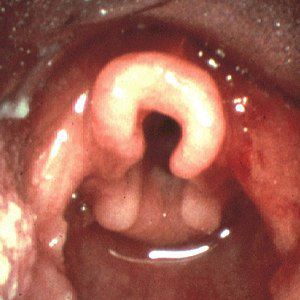

An exact cause is unknown, but experts believe it has something to do with the way the voice box develops in the womb. The muscles supporting the voice box may be too weak or relaxed. Additionally, GERD — which is common in babies with laryngomalacia — may make laryngomalacia symptoms worse